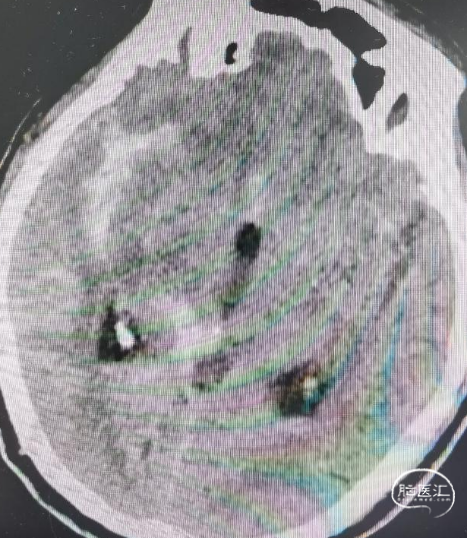

术前影像

CT显示广泛蛛网膜下腔出血,右侧侧裂池为著。

DSA示:右侧大脑中动脉分叉上干起始部宽颈动脉瘤,呈不规则分叶状,载瘤动脉管径纤细,角度锐利,载瘤动脉直径1.45mm,大脑中动脉直径2.26mm,动脉瘤大小约5.35mm×3.98mm×4.14mm。